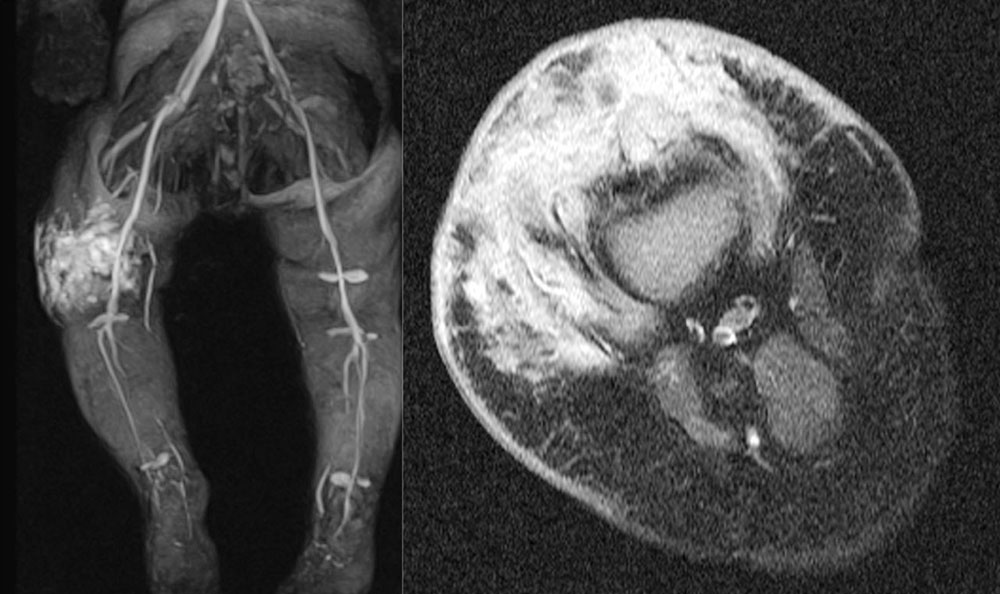

Positive reports of the use of sirolimus in individual case studies and smaller series of patients with extensive vascular malformations and corresponding severe clinical presentations have been published since 2011.

Sirolimus seems to be especially effective in the case of extensive, severe micro- or macrocystic lymphatic malformations.

There are also publications on the use of sirolimus to reduce gastrointestinal bleeding in venous malformation of the intestinal mucosa, especially in blue rubber bleb nevus syndrome. Reductions of the volume of the lesions have also been reported in this situation.

A questionable effect or no effect in reducing bleeding frequency and proliferation activity in severe, complicated arteriovenous malformations has also been reported. The treatment outcome in fast-flow malformations appears to be significantly smaller and could not be demonstrated in all studies. The reason for this may lie in the genetic basis of arteriovenous malformations where dysregulation of another signaling pathway (RAS/MAPK/ERK signaling cascade) seems to be affected. By contrast, in slow-flow malformations upregulation of the PIK3CA/AKT signaling pathway is causative in the development of vascular anomalies. Sirolimus (rapamycin) is a central inhibitor of this mammalian target of rapamycin (mTOR) pathway, which may explain its effect.